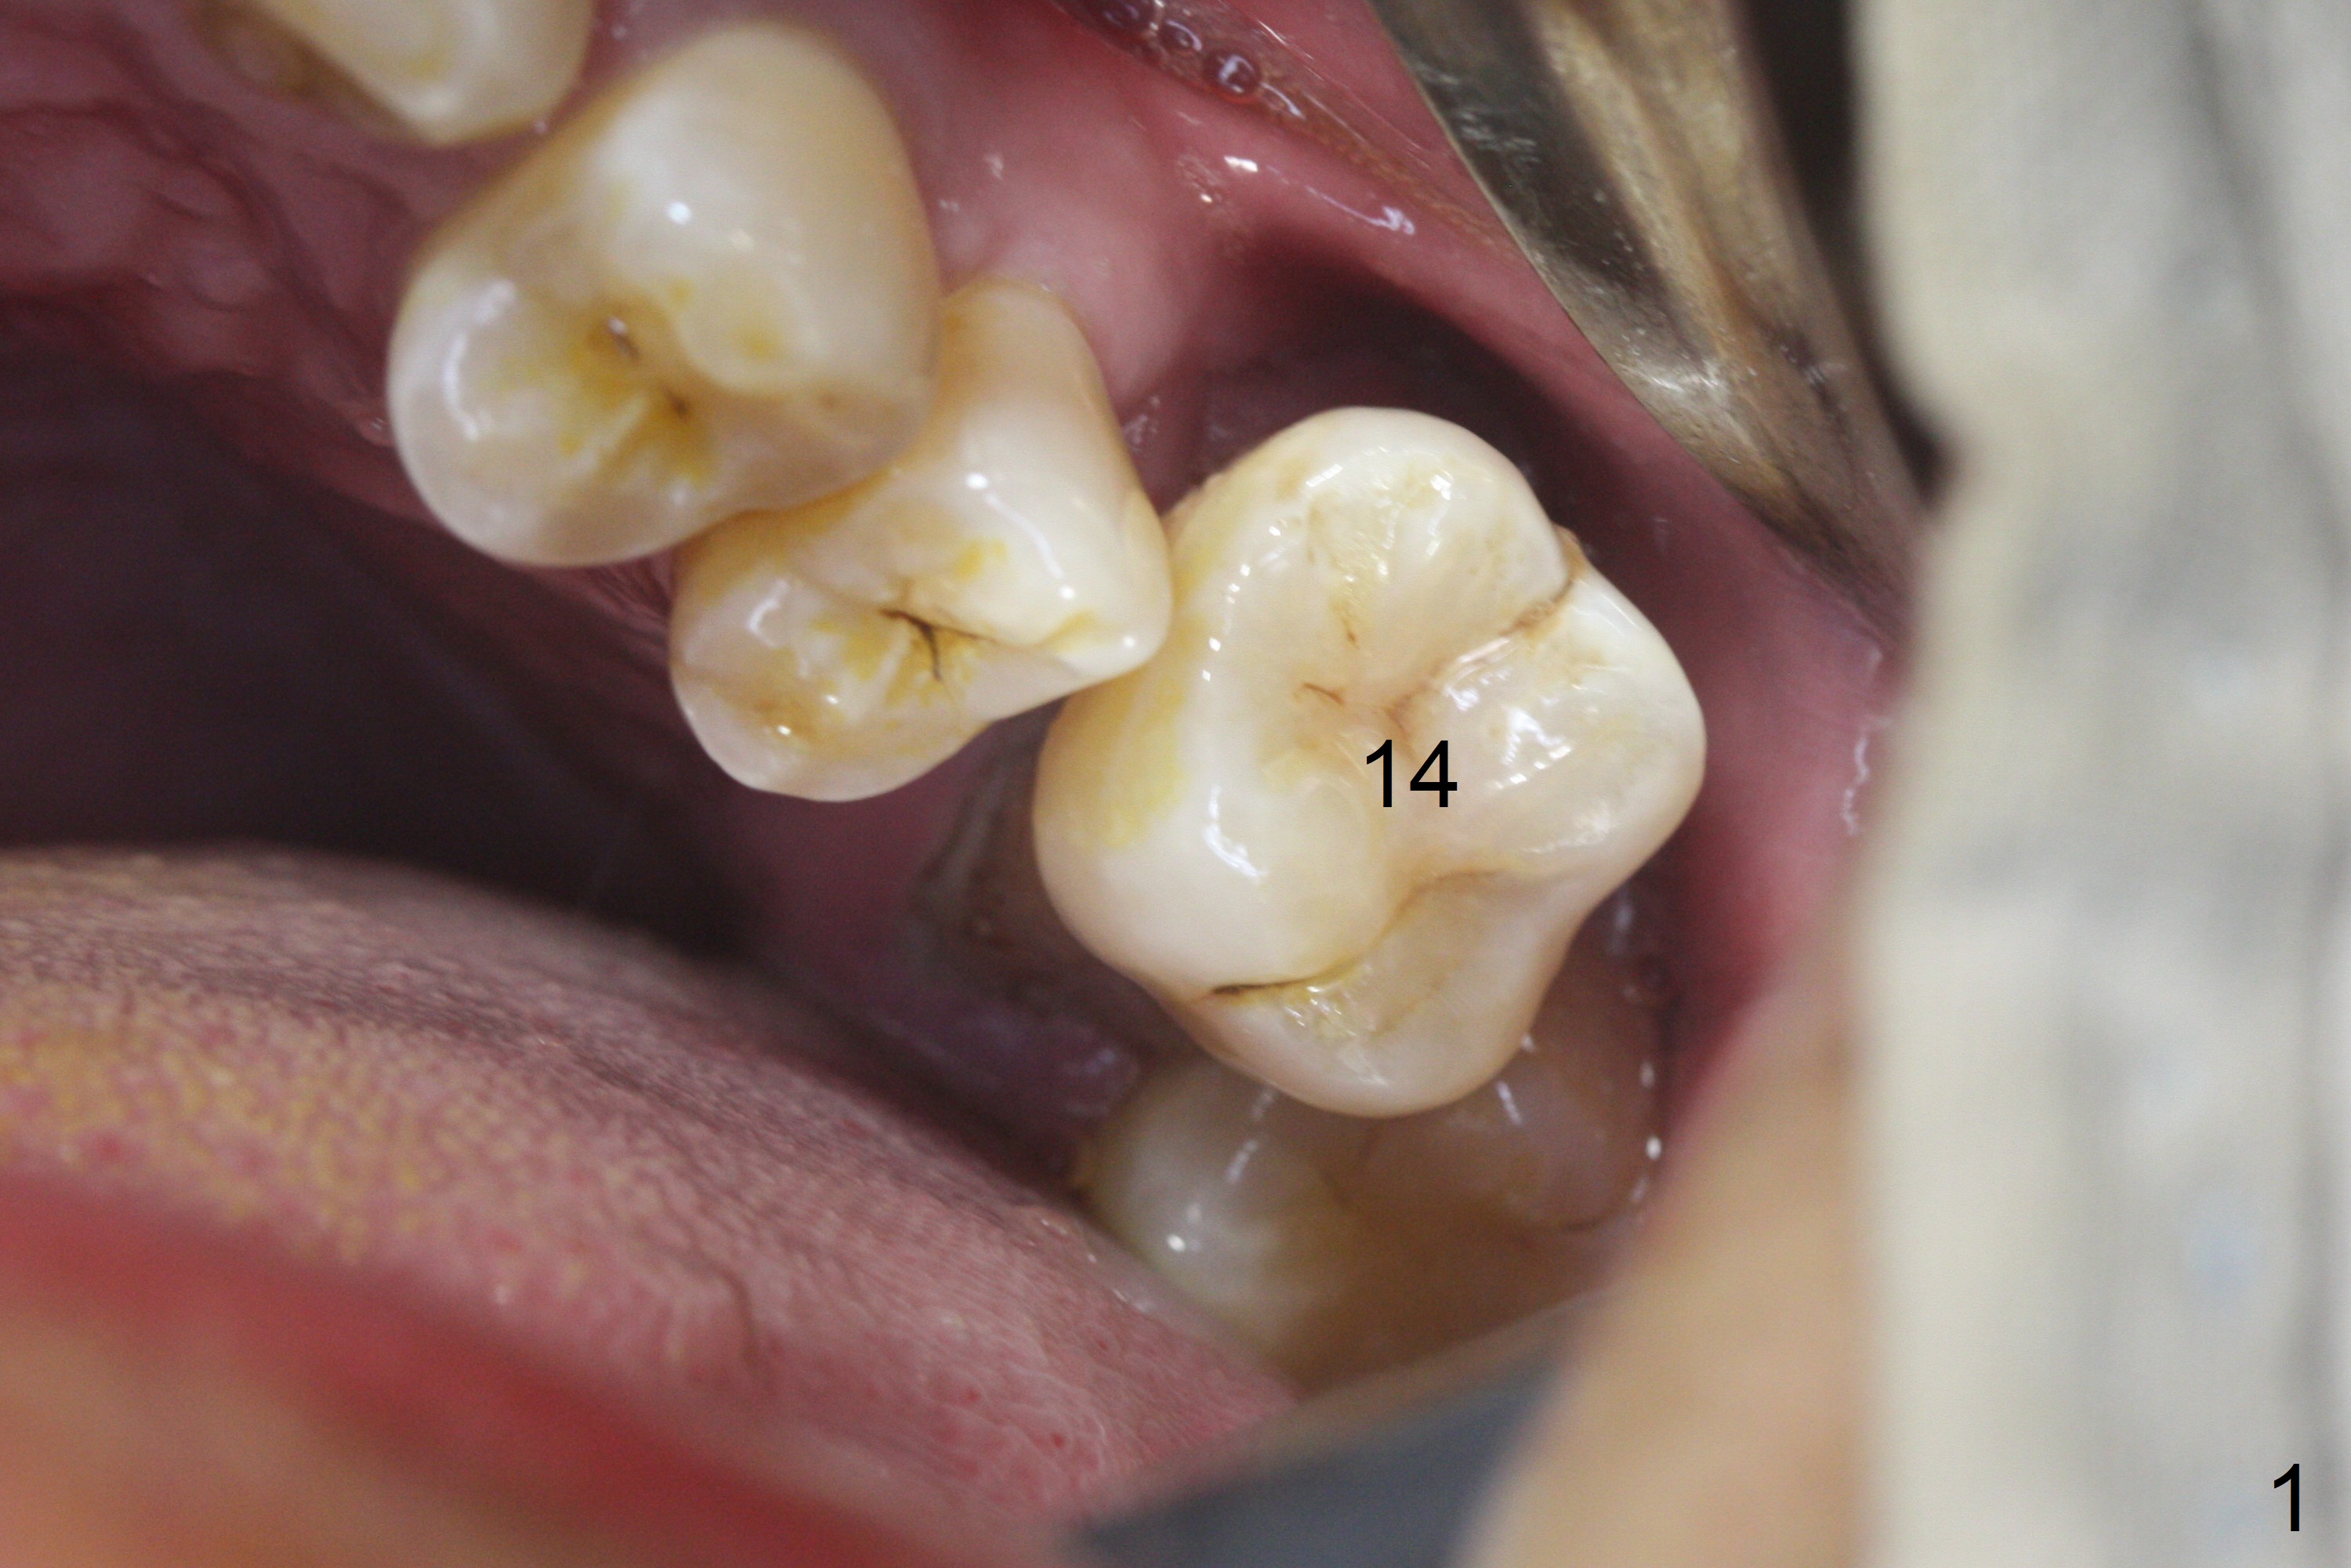

When the displaced tooth #14 (Fig.1) with palatal gingival recession (Fig.2) is extracted, the buccal plate is low, while the palatal one is lost.  Osteotomy is initiated in the bottom of the large socket with Marking Drill.  The bone turns bluish, suggesting thin bone (in fact less than 1 mm as well as low density).  Magic Sinus Lifter (Fig.3 *, Fig.4 blue area) is used for sinus lift (Fig.4 (red curved line: lifted sinus membrane; grey area: a portion of the lifted sinus floor), followed by insertion of a piece of PRF plug and Vanilla bone graft for sinus lift.  The osteotomy is enlarged lightly with 4.8 mm Magic Drill (compare black strips between Fig.4,5).  A 5x9 mm dummy implant (Fig.5 green) is dislodged into the sinus.  The lifted sinus membrane holds the implant in place.  The black thin strip in Fig.5 and black circle in Fig.6a (occlusal view) represents the osteotomy.  After increase in the osteotomy with Lindamann bur (Fig.6b red circle), the implant (Fig.6c green) is retrieved with endodontic forceps (Fig.6c two blue dots (beaks of the forceps); Fig.7,8).  With the enlarged osteotomy (Fig.6d), a 6x9 mm dummy implant is placed deep (Fig.9).  The definitive implant is 6.5x11 mm with insertion torque ~ 15 Ncm (Fig.10).  With placement of a healing screw and further placement of allograft (Fig.11 *), the socket is closed with PRF membrane and collagen plug (Fig.12).